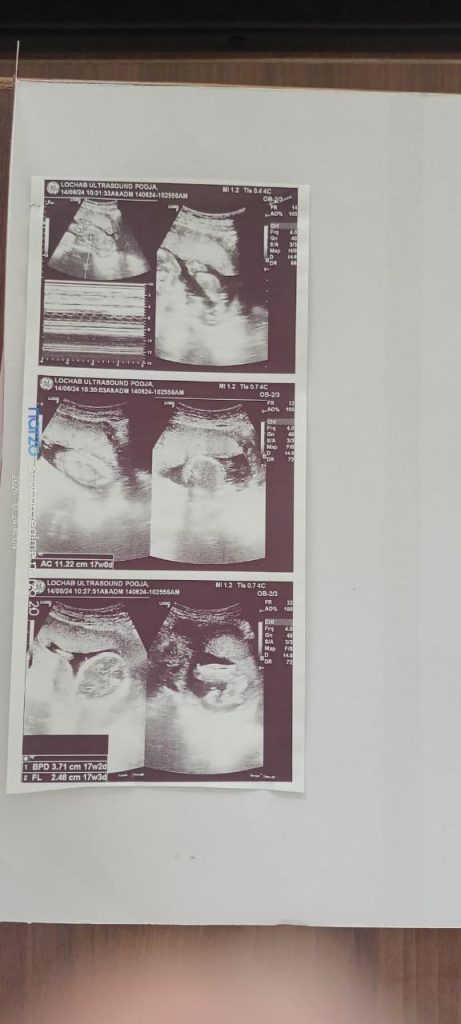

| 6 | 06/08/24 | Pain in lower back Desire sour things USG LOWER ABDOMEN-14/6/2024Findings are suggestive of single live fetus of about 17 weeks +- 2 weeks of gestation USG LOWER ABDOMEN-25/7/2024Findings are suggestive of single live fetus of about 22 weeks +- 2 weeks of gestation | Medorrhinum 1M (Stat dose)Kali phos 30 HS |

| 7 | 16/10/24 | Aching pain in back and bones of extremities weaknessconstipation USG LOWER ABDOMEN-15/10/2024Findings are suggestive of single live fetus of about 32 weeks +- 2 weeks of gestation | Eupatorium perfoliatum 200 BD x3days |